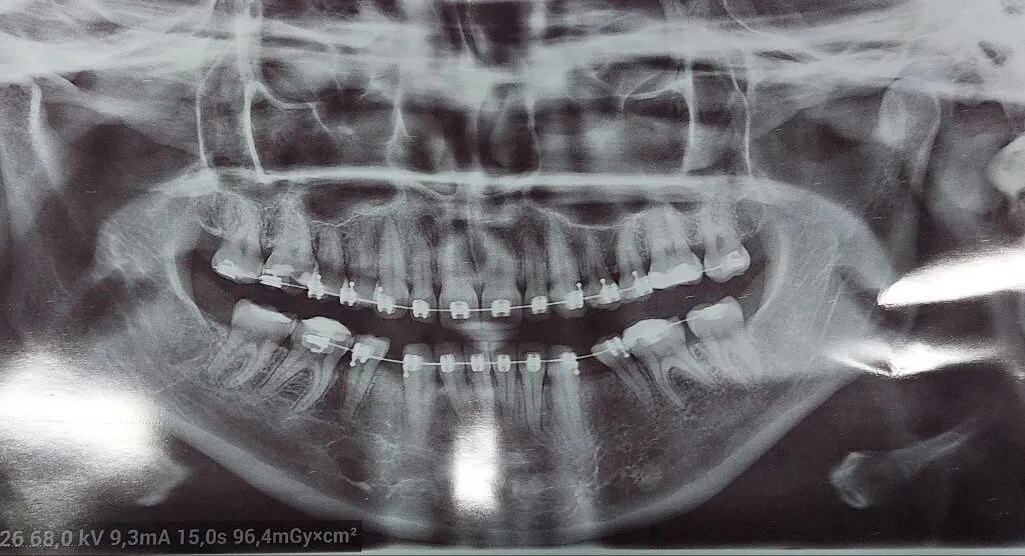

У квітні 2025 року брекет-систему Сніжані встановили на верхню щелепу, а за місяць почали займатися нижньою. Саме тут і почалися проблеми.

Із нижньої щелепи у дівчини постійно вилітала дуга та відпадали брекети. А так бути не повинно. Тому вона знову звернулася до лікарки Василенко. Наприкінці липня дівчині вирвали два зуби — нижні 4-ки. Стоматологиня сказала, що це має вирішити ситуацію. Крім того, після видалення зубів жінка почала стягувати брекетами інші зуби, аби закрити простір, що утворився на місці видалених.

Проте брекети продовжили відпадати й далі. У вересні на прийомі стоматологиня припустила, що причиною цьому може бути суглоб або щелепна кістка, що заважають зубам рухатися. У листопаді лікарка призначила дівчині одягати на ніч еластики, аби ті швидше стягнули зуби.

— Лікар також сказав, що у моєму випадку не було ніякої необхідності виривати нижні 4-ки. І при цьому лікарка неправильно потягнула зуби еластиками, тому так і сталося.

- продовжити стягувати зуби. Але у такому випадку щілини все одно залишаться, тож доведеться донарощувати здорові зуби. І немає гарантії, що у майбутньому це не призведе до випадіння інших зубів;

- або ж переробляти усе заново. Розтягувати ті зуби, що їх почали стягувати після видалення, і на місце видалених зубів ставити імпланти.